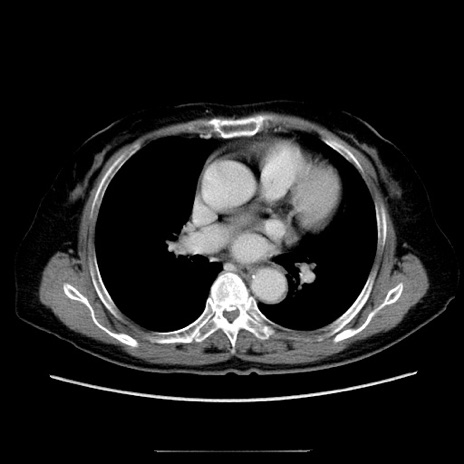

症例5(横断像)

【症例】70歳代女性

【主訴】お腹が張る

【現病歴】1週間くらい前から腹部膨満の自覚あり。昨日夜から増悪したため、本日救急外来受診。

【身体所見】意識清明、BT 36.5℃、BP 165/106mmHg、HR 80bpm、SpO2 98%、腹部:膨満、軟、自発痛・圧痛なし、触診にて不快感あり、腸蠕動音:減弱

【データ】WBC 12600、CRP 1.04